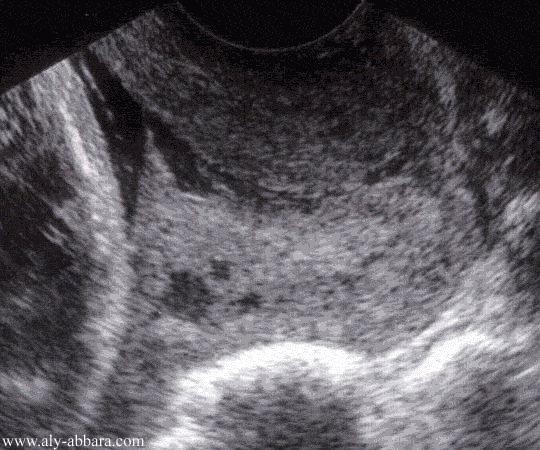

Coupe échographique du col utérin au cours du

troisième trimestre de la grossesse

Consulter : Incompétence cervico-isthmique (béance de l'orifice interne du col utérin)